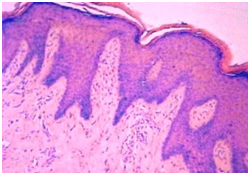

Figure 4 Psoriasiform epidermal hyperplasia with chronic candidiasis.

Histopathology: elucidates an epithelial entrenchment by the Candida hyphae and fungal spores accompanied with chronic inflammation, hyperkeratosis, parakeratosis and orthokeratosis.1,6 Hyperplasia with Candida inflammation generally elucidates a dysplastic metamorphosis.1,6

Chronic candidiasis: Prominent hyperkeratosis, pseudo-epitheliomatous hyperplasia, compressed orthokeratosis and a scaly encrustation may appear.5,6 Fungal spores and hyphae may be delineated in the absence of a Periodic acid Schiff (PAS) stain. Granulomatous dermatitis may also emerge with indeterminate granulomas comprising of lymphocytes, plasma cells, epitheloid cells and sporadic giant cells.5,6